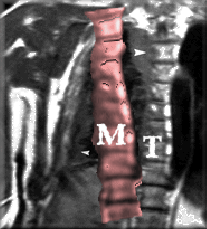

To use an example, Figure [*] illustrates this approach. The model $\mathbf{M}$ is positioned in the image close enough to its target, which is the spine. The model contains knowledge about ways in which it is allowed to deform. Model parameters are repeatedly changed until the model (ideally) overlaps the target images. Then, by extracting model parameters, knowledge can be gained about the image itself. This method has proven useful in various areas, including industrial inspection, motion analysis [], face recognition [,], and medical image understanding [].

Figure: target spine image $\mathbf{T}$, overlaid by a high-level representation (the model $\mathbf{M}$), which searches for an improved fit in the target image by transforming itself.